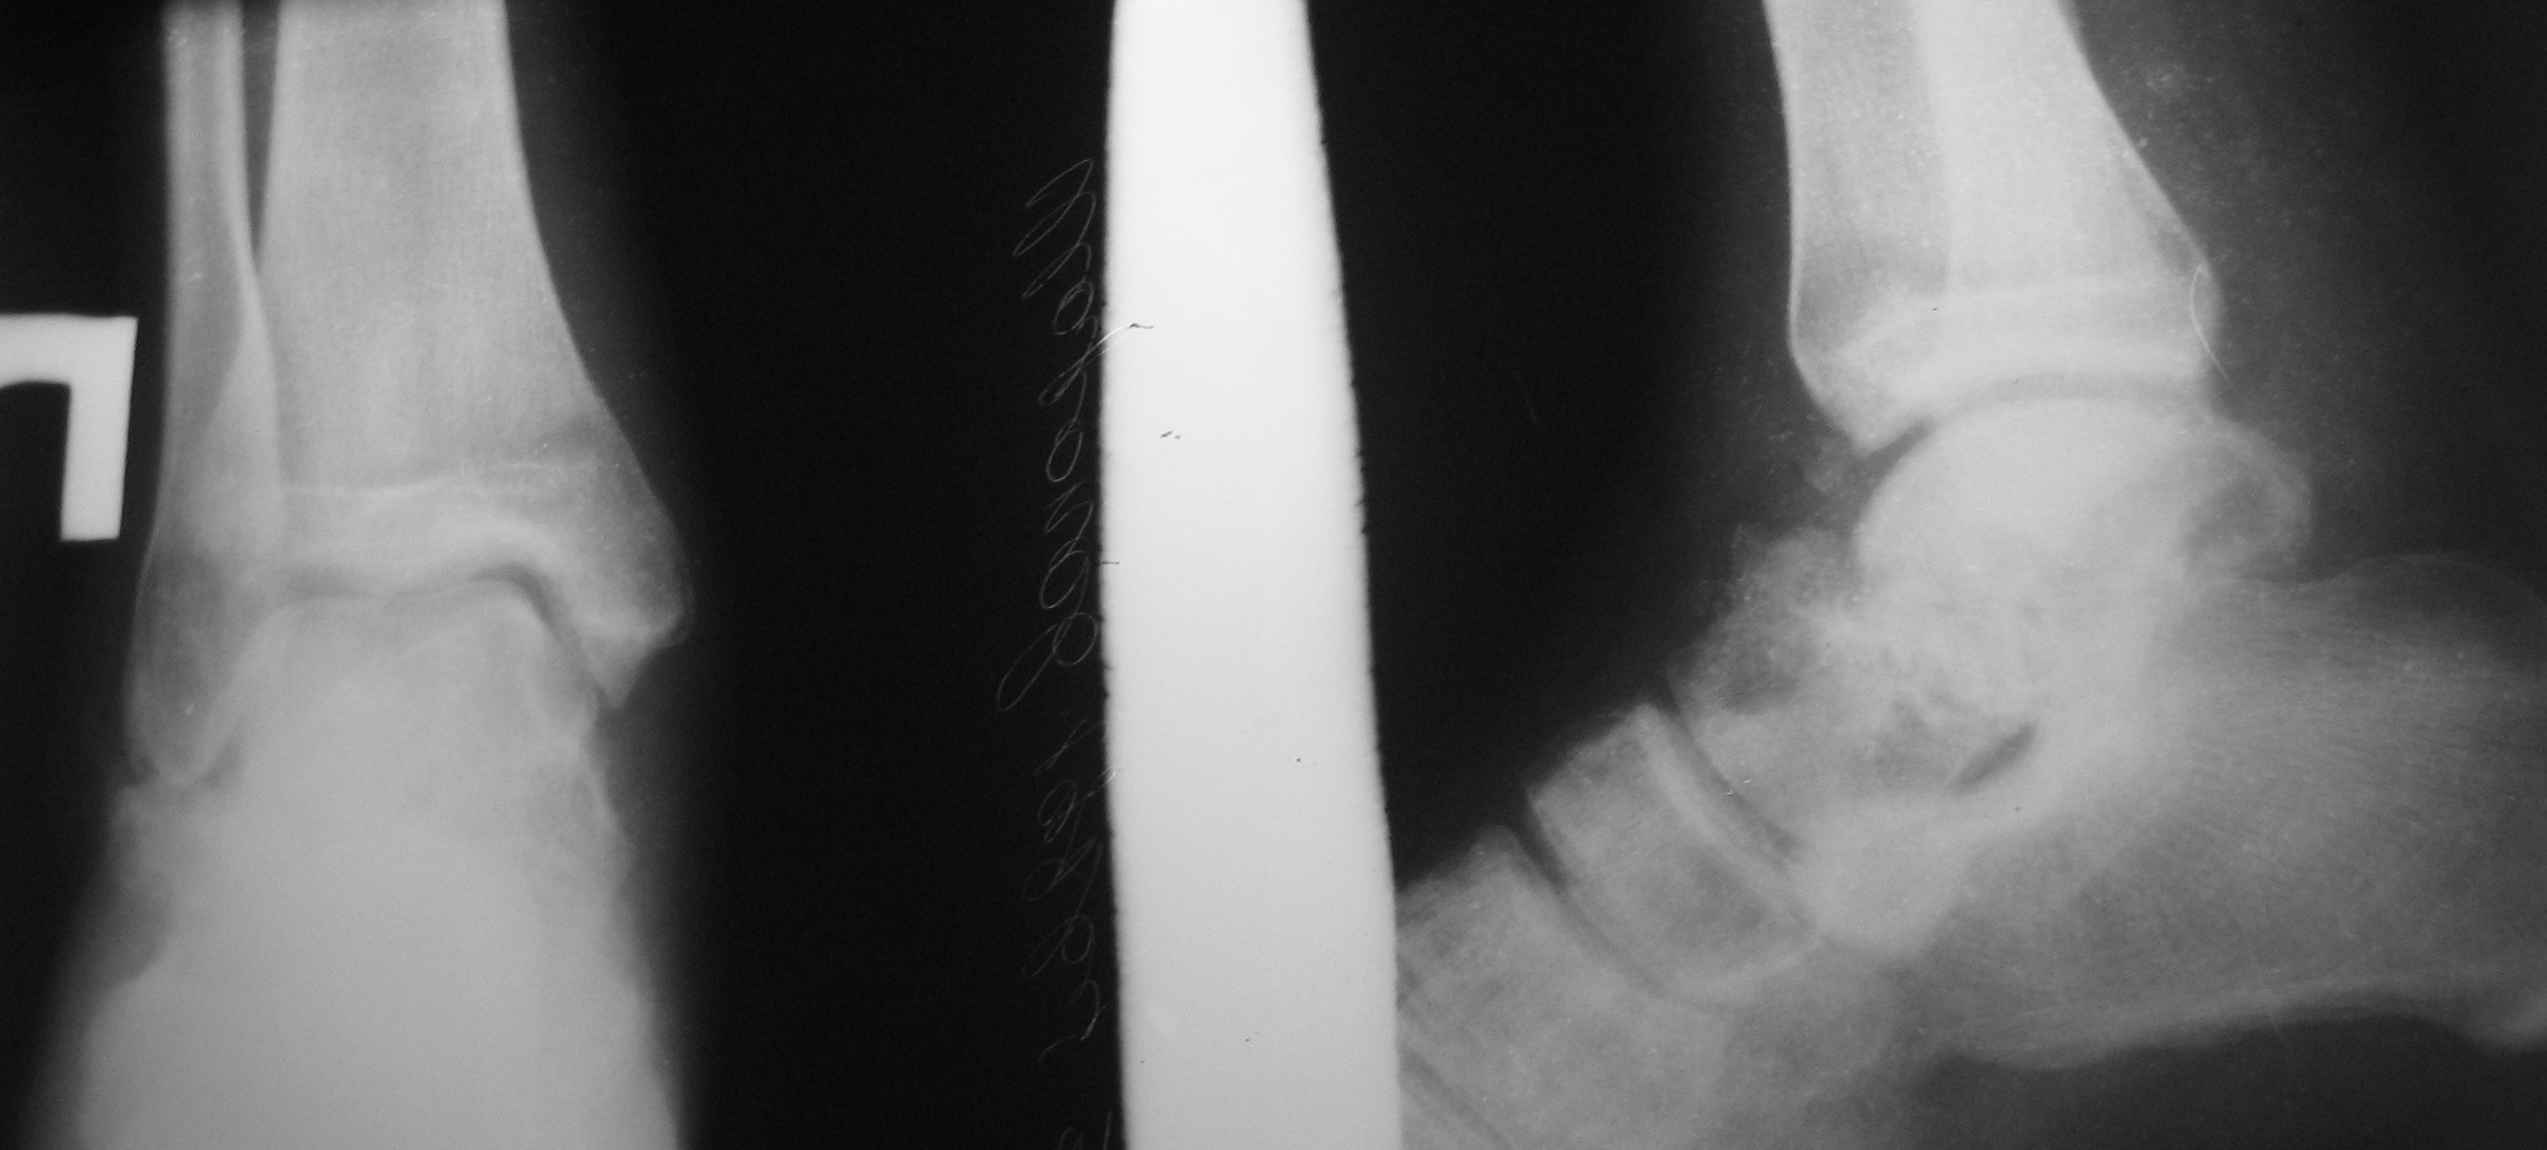

Обратился б-ной С. 1986г.р с застарелыми переломами надколенника и таранной кости, сросшийся переломом обеих локтевых отростков. 25.07.07.г. упал с 6-го этажа. Оперирован в г. Тюмени в гор. б-це 15.08.07.г.:Судя по рентген снимкам остеосинтез обеих локтевых отростков по Веберу, остеосинтез правого надколенника (каким способом не понял ), фиксация гипсовой повязкой правой н/к, гипс снят через 40 дней (со слов б-го.) Обратился в начале декабря, с жалобами на отсутствия активного разгибания в пр. коленном суставе, боли и отечность в обл. пр. г/стоп. сустава и стопы. Больной ходит самостоятельно с палочкой, сильно хромает на правую ногу, гипотрофия квадрицепса, активное разгибание abs, в обл. г/стопного сустава умеренная отечность, актив. и пассив. движения почти в полном объеме, слегка болезненная, при осевой нагрузке боль усиливается, Сделана Р-графия локтевых суставов, пр. коленного и г/стопного суставов. Спицы и проволоки из локтевых отростков удалены. Я больному обещал, что выйду на форум, посоветуемся и вместе решим, что делать. 1. Из -за ретракции м/тканей репозиция отломков надколенника не удается, что делать? 2. Перелом таранной кости- вроде схватка имеется но с кистозными изменениями, может не трогать? Заранее благодарю !!

po moemu na snimke viden avascul necrosis of talar bone . lechit v cootvetstvii .

Надо "трогать". Подтаранный артродез очень показан и синтез перелома так же.

не согласен с последним оратором :)

показание к подтаранному артродезу ( как и к артродезу голеностопа) только одно - сильнейшая боль в стопе. Артродез - дело стремное, и больному надо четко объяснить, что то, что делается - это последняя мера, позволяющая избежать ампутации, и что следующая операция после артродеза стопы, если он будет неудачным - ампутация. так что , на мой взгляд , правильная тактика по поводу тарана - объяснить больному всю правду по поводу стопы и предложить приходить на операцию, когда боль в стопе не позволит ему ходить даже с палочкой.

Уважаемый Абдурашид!Что касается перелома таранной кости - нет возможности сделать КТ?С чем связана хромота?По-видимому,пациента в первую очередь беспокоит боль при ходьбе,видимо,придется делать артродез.